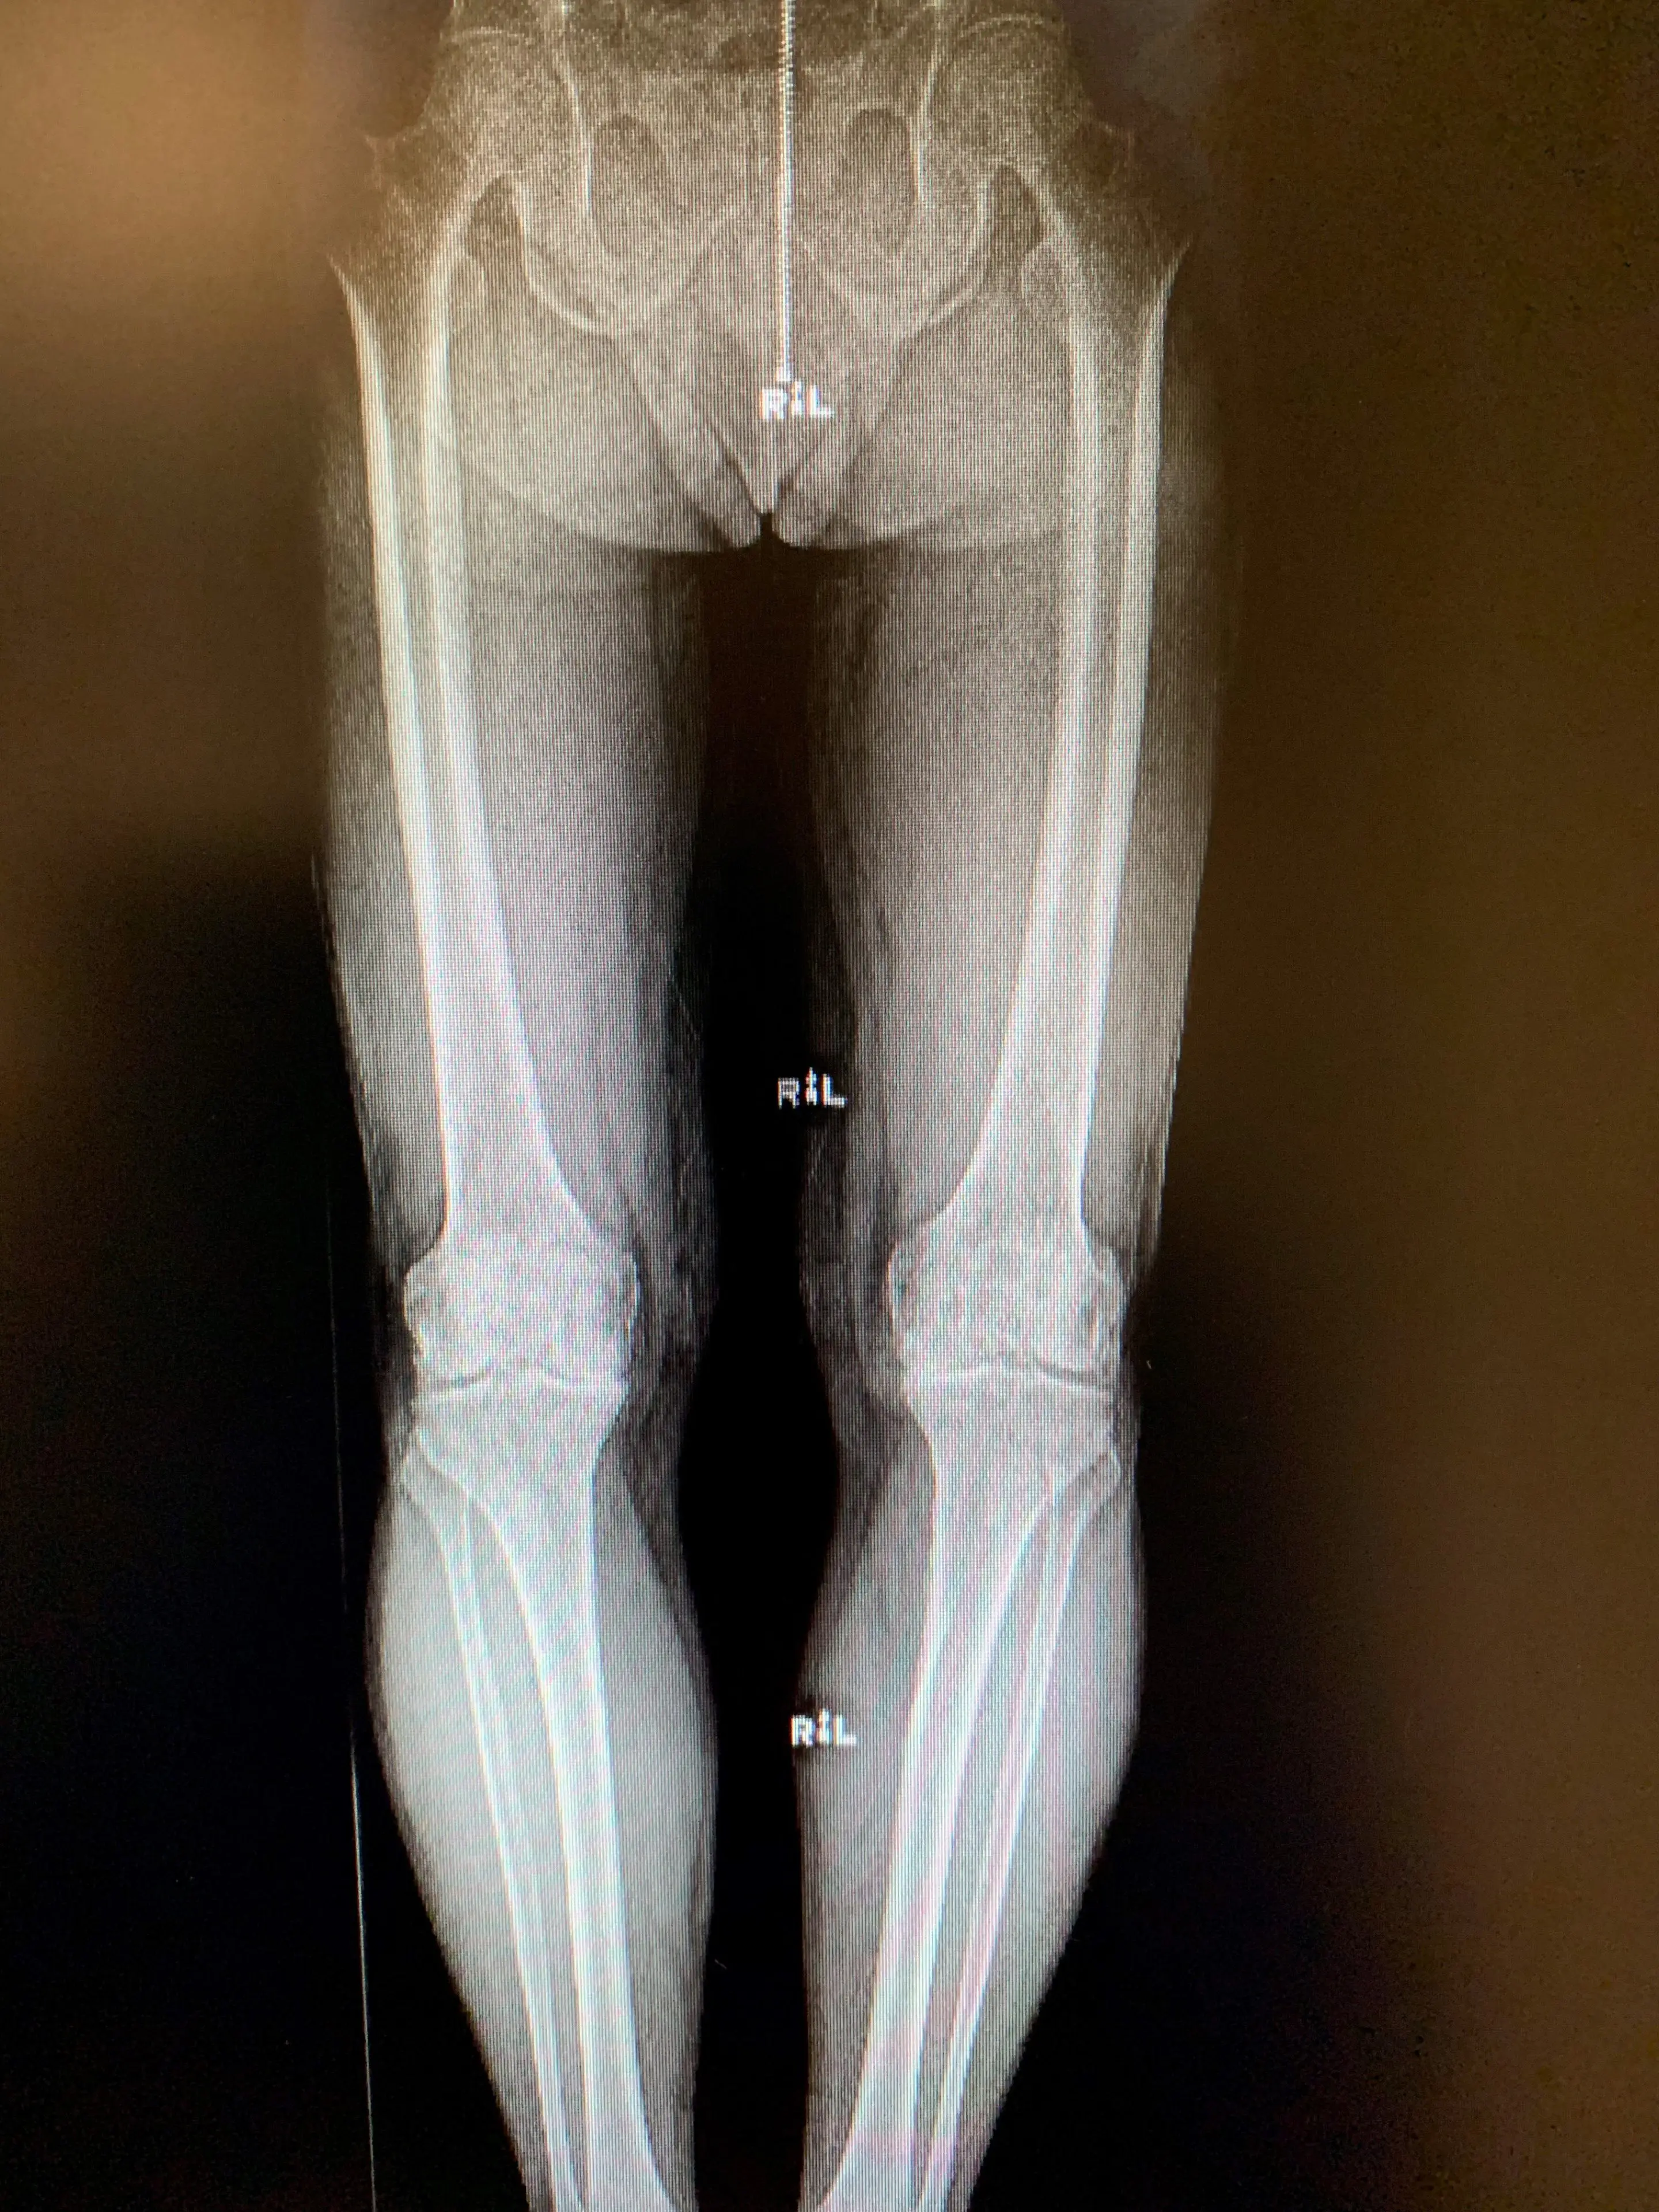

Post-opSimultaneous bilateral Unicondylar Knee replacement in 67 year old maleb

Simultaneous bilateral Unicondylar knee replacement in a 67-year-old male.